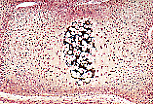

Le point d'ossification apparaît au centre de la maquette cartilagineuse où les chondrocytes prolifèrent, s'hypertrophient et se vacuolisent dans des chondroplastes agrandis.

La substance cartilagineuse dans cette zone centrale hypertrophiée et vacuolisée se calcifie ensuite, ainsi que l'illustre cette coloration de von Kossa.

Au sein de la matrice calcifiée , les chondrocytes involuent et disparaissent. Les deux feuillets (externe et interne) du périchondre sont reconnaissables sur cette illustration.

En regard du cartilage calcifié, se dépose en périphérie une mince gaine de tissu osseux : la virole osseuse périchondrale.